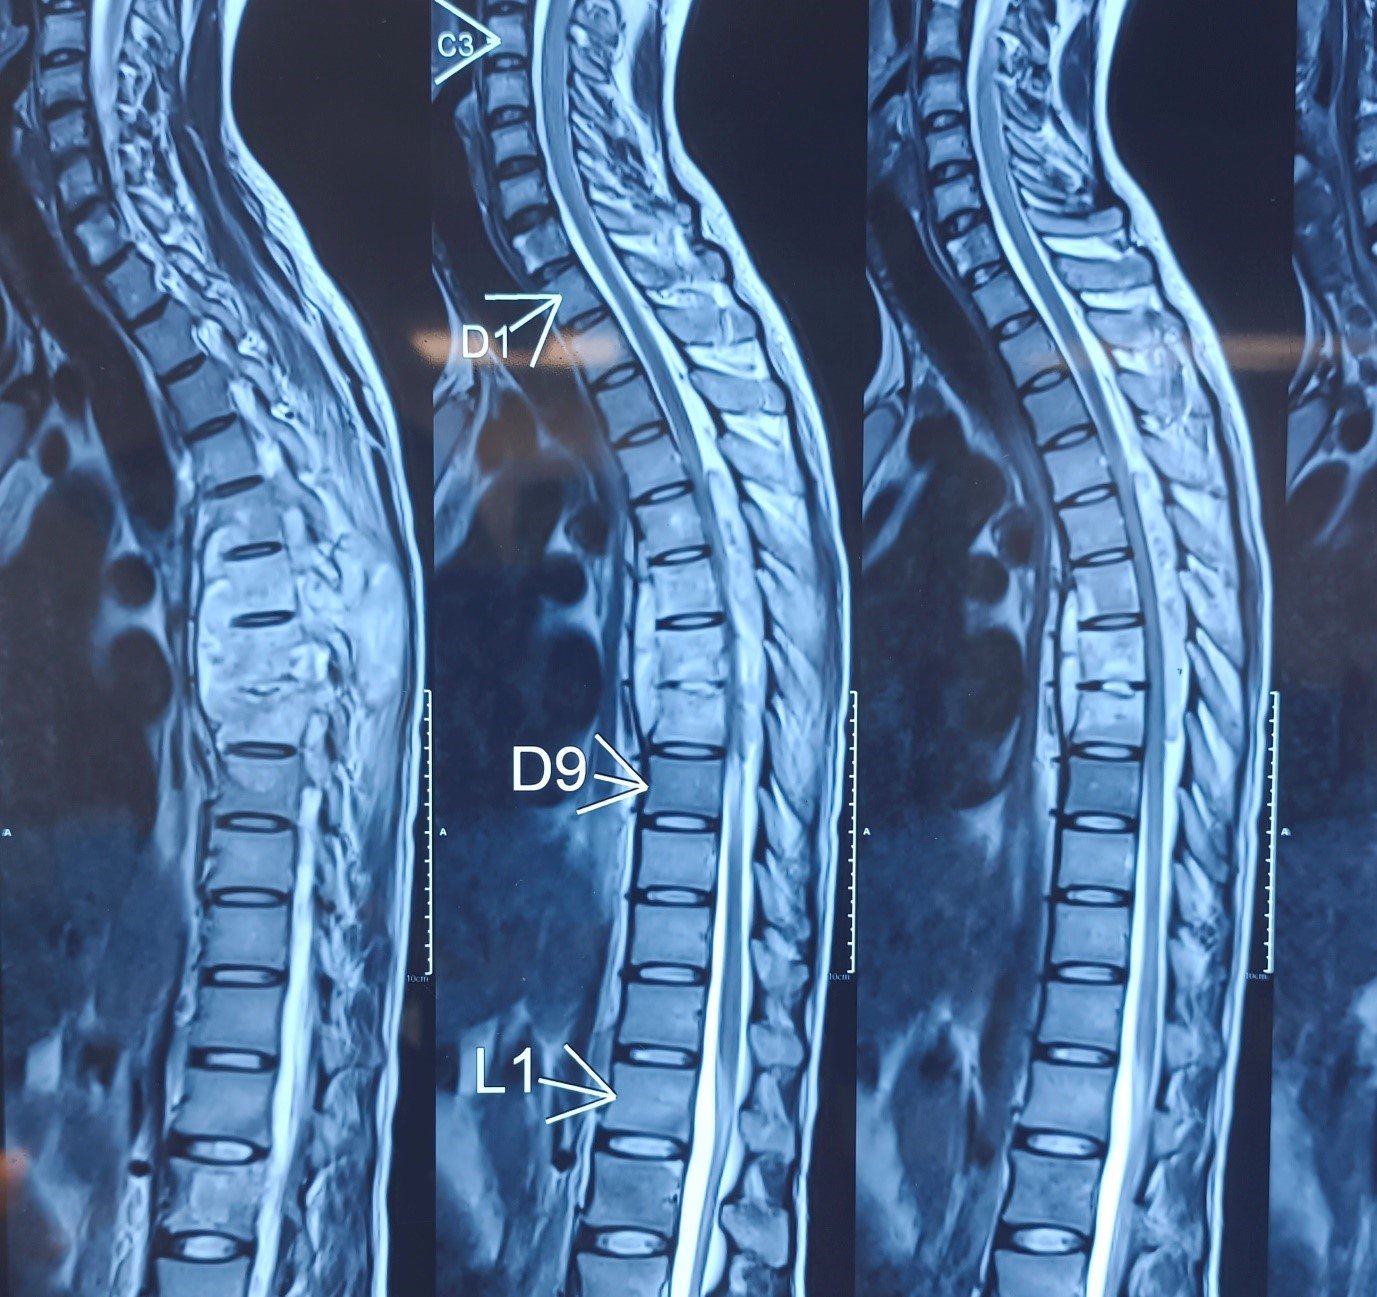

Cervical Disc Prolapse with Spinal Cord Compression

Special Cases Cervical Disc Prolapse with Spinal Cord Compression Condition:Cervical disc prolapse in which the herniated disc compresses the nerve roots and spinal cord, often associated with spinal cord edema. Symptoms:Neck pain, numbness in hands, weakness, difficulty in walking, and coordination problems. Treatment:Anterior Cervical Discectomy and Fusion (ACDF) – The…